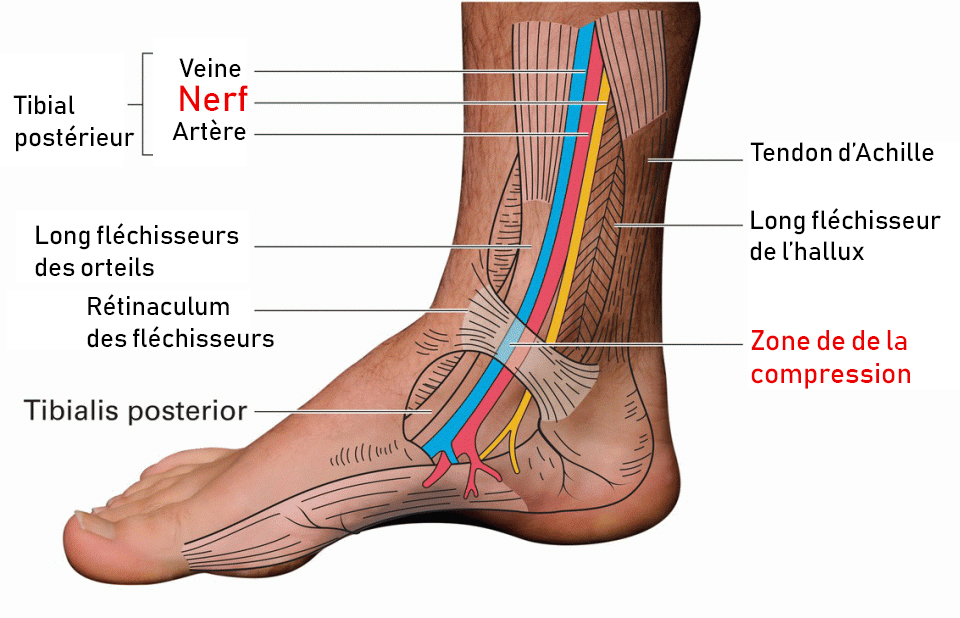

Syndrome du tunnel tarsien

Il s’agit d’une pathologie douloureuse du pied en lien avec une compression du nerf tibial postérieur. Ce dernier passe par l’arrière du mollet au talon et à la plante des pieds en passant à travers un canal fibreux : le « canal tarsien ».

Les douleurs peuvent typiquement s’accompagner de picotements ou d’une sensation de brûlure. Dans certains cas, une perte de la sensibilité de la face interne/plantaire du pied peut apparaître.